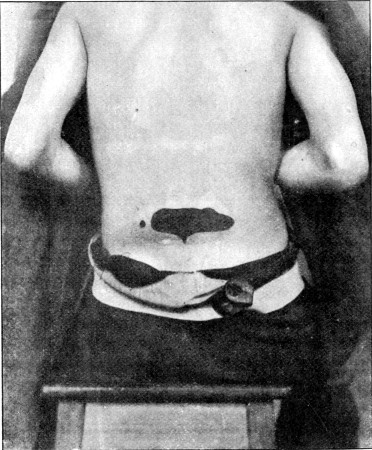

44. Explosive Wound of Back100

45. Dead Men on Field of Battle102